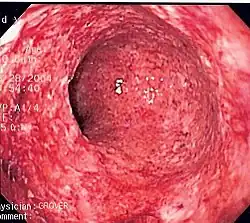

Chronisch-entzündliche Darmerkrankungen

Zu den chronisch-entzündlichen Darmerkrankungen werden üblicherweise Morbus Crohn und Colitis ulcerosa gezählt, die in Deutschland mit jeweils 5–6 Neuerkrankungen pro 100.000 Einwohner pro Jahr etwa gleich häufig auftreten. Kennzeichnend ist eine dauerhafte (chronische) Immunreaktion in der Darmwand, die in Schüben auftritt. Bei beiden Erkrankungen sind die Auslöser und Mechanismen der Krankheitsentstehung noch unklar.[38] Franz Alexander zählte sie 1950 zu den sieben psychosomatischen Krankheiten, den „Holy Seven“, diese These gilt inzwischen als überholt. Mittlerweile wurden auch genetische Faktoren identifiziert, die bei der Entstehung der Krankheiten eine Rolle spielen könnten. Morbus Crohn und Colitis ulcerosa unterscheiden sich hinsichtlich des Krankheitsverlaufs und ihres Erscheinungsbildes (Morphologie).

Der Morbus Crohn ist die Entzündung der ganzen Darmwand mit allen Schichten, weshalb es häufig zu Fisteln (beispielsweise Analfisteln) kommt. Grundsätzlich kann der gesamte Verdauungstrakt befallen sein, typischerweise betrifft die Entzündung aber den Endabschnitt des Dünndarms (Ileum) und den Dickdarm. Die Entzündung breitet sich nicht kontinuierlich vom Entstehungsort aus, sondern „springt“ von Abschnitt zu Abschnitt.[39] Der Morbus Crohn heilt häufig nur unvollständig ab und ist durch eine hohe Rezidiv-Rate, also wiederkehrende Entzündungen, gekennzeichnet.[40]

Bei der Colitis ulcerosa beschränkt sich die Entzündung dagegen auf die Schleimhaut. In der Regel beginnt die Entzündung akut im Rektum und breitet sich von dort kontinuierlich auf die restlichen Dickdarmabschnitte aus. Ist der ganze Dickdarm befallen, ist von einer Pancolitis die Rede. Bei etwa 10 bis 20 % der Pancolitiden kommt es zur sogenannten „Backwash-Ileitis“, bei der die Entzündung auf das Ileum des Dünndarms übergreift.[41] Auch die Colitis ulcerosa verläuft rezidivierend, also mit wiederkehrenden Schüben. Zwischen den Schüben heilt der Darm in der Regel aber vollständig ab.[42] Beim akut fulminanten Verlauf ist das toxische Megacolon eine seltene, aber lebensbedrohliche Komplikation mit der Gefahr einer eitrigen Bauchfellentzündung. Colitis ulcerosa erhöht das Risiko, an Darmkrebs zu erkranken.[43] Durch eine Kolektomie, Entfernung des Dickdarms, ist Colitis Ulcerosa theoretisch heilbar,[44] es wird dann hierfür ein Stoma bzw. ein Pouch erstellt.

Zur endoskopischen Untersuchung stehen verschiedene Verfahren zur Verfügung. Das Rektoskop ist ein starres Endoskop, das nur zur Beurteilung von Analkanal und Rektum geeignet ist. Eine Sigmoidoskopie zur Beurteilung des Darms bis zum Colon sigmoideum kann mit einem bis zu 60 cm langen, flexiblen Endoskop erfolgen.[54] Die Koloskopie (Darmspiegelung) ist die endoskopische Untersuchung des gesamten Dickdarms mit einem langen Endoskop. Sie gilt als Goldstandard für die Beurteilung der Schleimhaut. Mit diesem Verfahren können nicht nur sichtbare Veränderungen beschrieben, sondern auch Proben entnommen (biopsiert) und kleine therapeutische Eingriffe durchgeführt werden (beispielsweise die Entfernung eines Polypen).[55]